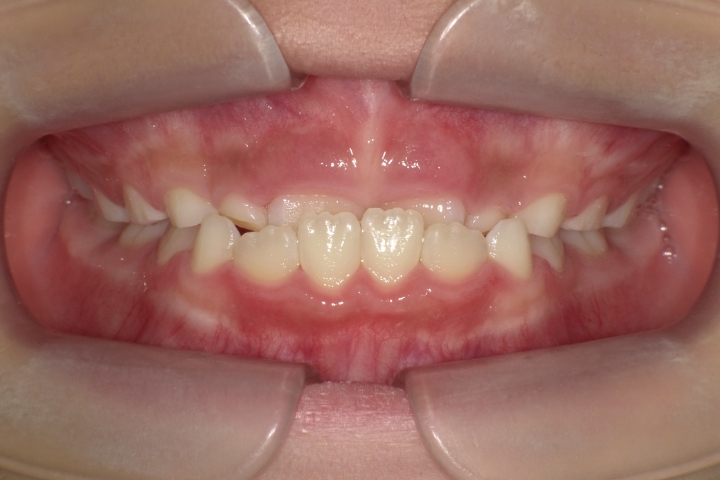

当医院では、歯並びに対する各種治療を行っております。

セファロ写真(横顔のレントゲン)や歯型を分析し、それぞれにあった治療プランをご提案致します。

また、ワイヤー矯正やインビザライン矯正(マウスピース矯正)等、症例に合わせて行っております。

お子様においては、プレオルソ治療も行っております。受け口や出っ歯等、早期に解決すべき歯並びに対して、高いコストパフォーマンスを上げております。